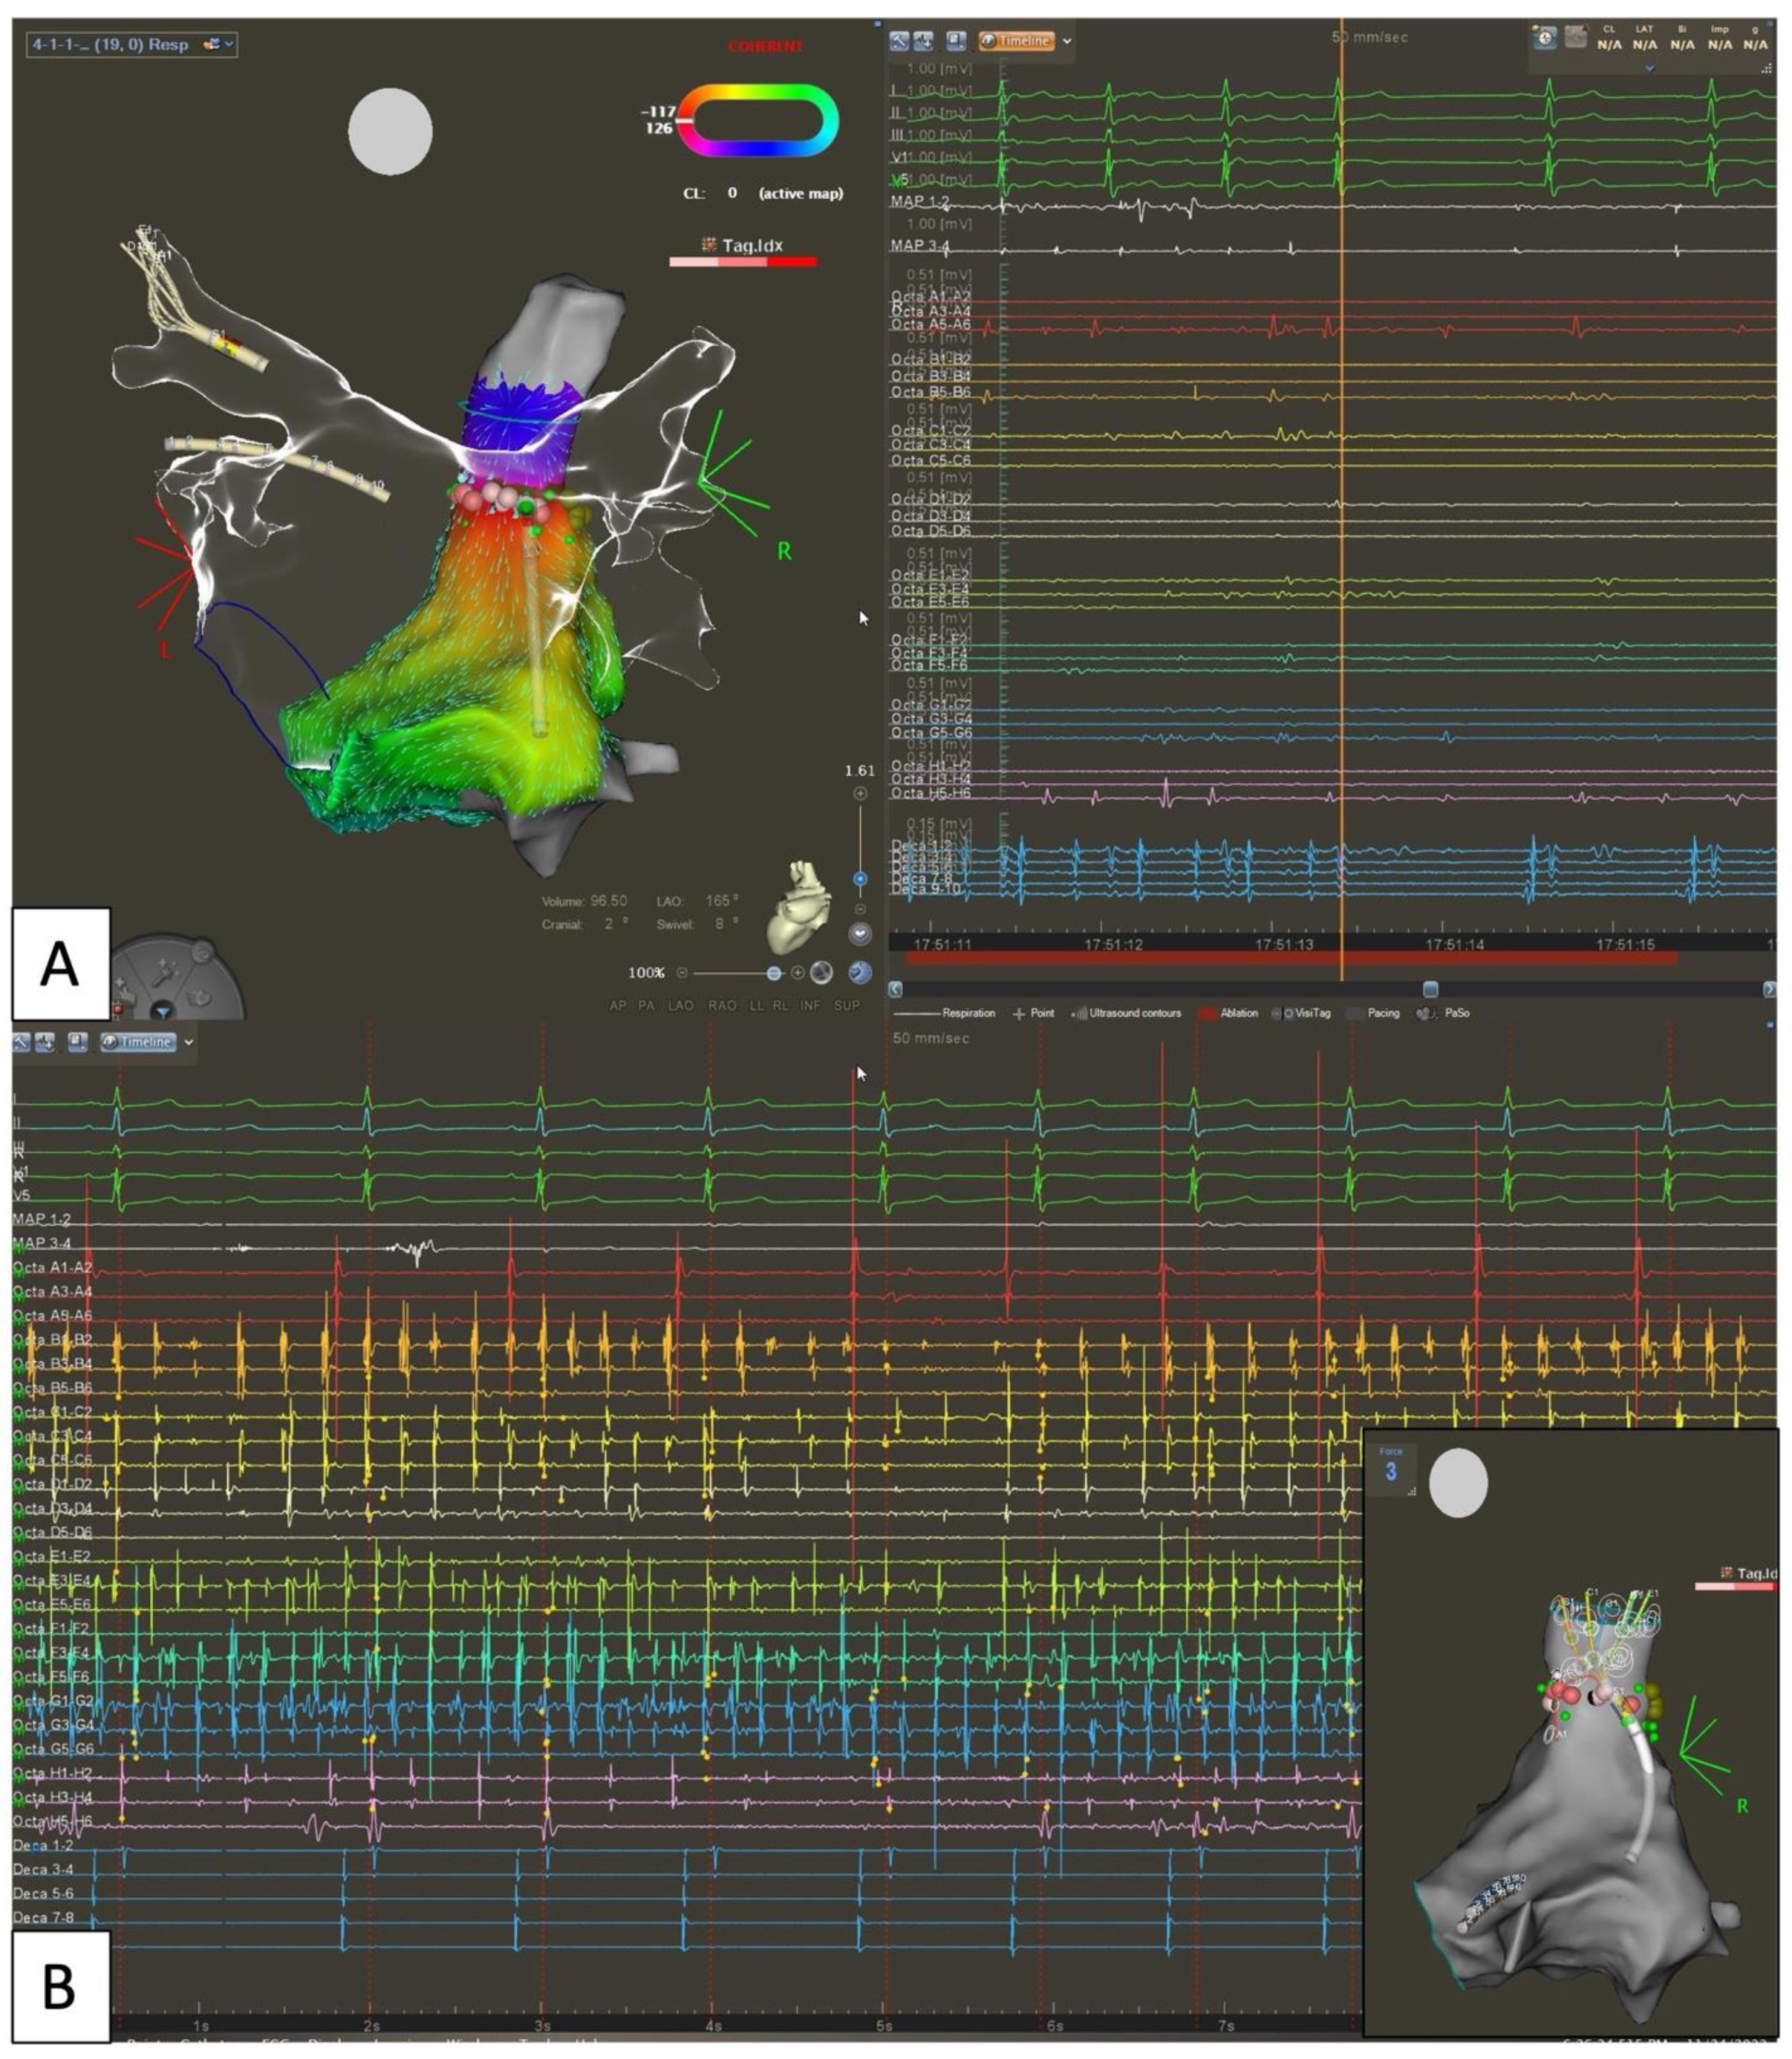

- Madaffari, A.; Knecht, S.; Spies, F.; Schaer, B.; Kühne, M.; Sticherling, C.; Osswald, S. Epicardial Connection: The Achilles Heel of Gap Mapping After Wide Antral Pulmonary Veins Isolation. JACC Clin. Electrophysiol. 2019, 5, 1356–1357. [Google Scholar] [CrossRef] [PubMed]

- Cabrera, J.A.; Ho, S.Y.; Climent, V.; Fuertes, B.; Murillo, M.; Sánchez-Quintana, D. Morphological Evidence of Muscular Connections between Contiguous Pulmonary Venous Orifices: Relevance of the Interpulmonary Isthmus for Catheter Ablation in Atrial Fibrillation. Heart Rhythm 2009, 6, 1192–1198. [Google Scholar] [CrossRef]

- Ho, S.Y.; Sánchez-Quintana, D. The Importance of Atrial Structure and Fibers. Clin. Anat. 2009, 22, 52–63. [Google Scholar] [CrossRef]